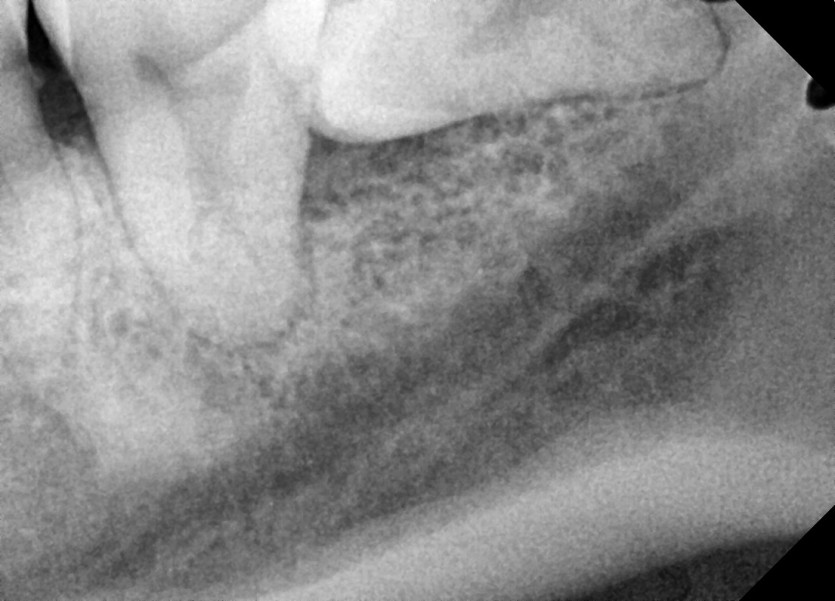

#38 사랑니 발치

구강 외과 전문의가 당일 발치했습니다.